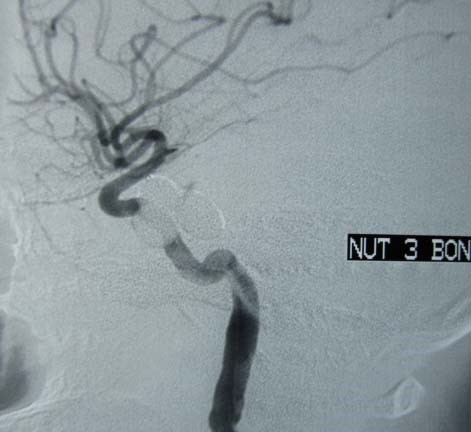

Phương pháp can thiệp nội mạch là phương pháp sử dụng bóng hoặc vòng xoắn kim loại dưới trợ giúp vi ống thông đưa đến chỗ luồng thông rồi bơm bóng hoặc thả vòng xoắn kim loại làm tắc luồng thông mà vẫn bảo tồn được động mạch cảnh trong. Có thể thả một hoặc nhiều bóng nếu luồng thông lớn. Với các trường hợp lỗ rách phức tạp, nếu không điều trị bảo tồn được động mạch cảnh trong, có thể tiến hành nút tắc mạch mang ở phía trên và dưới luồng thông, hoặc gây tắc qua đường tĩnh mạch. (Hình 1)

Nút thông động mạch cảnh xoang hang: a- Hình lồi đỏ mắt trái sau chấn thương. b- Hình CLVT thấy lồi mắt trái. c- Hình Siêu âm Doppler thấy giãn đảo chiều dòng chảy tĩnh mạch mắt. d- Hình thông trực tiếp động mạch cảnh xoang hang, luồng thông lưu lượng trung bình. e- Sau nút bằng 3 bóng, tắc hoàn toàn luồng thông. f- Hình kiểm tra sau nút luồng thông, mắt trái xẹp hết lồi.